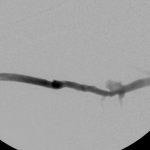

- Right arm venogram post intervention: complete elimination of the stenosis.

Then I dilated the brachial venous stenosis and probed through and dilated the right brachiocephalic vein. The brachial venous dilation proved optimal, but there was residual stenosis of the RBCV that I resisted stenting at the same setting.